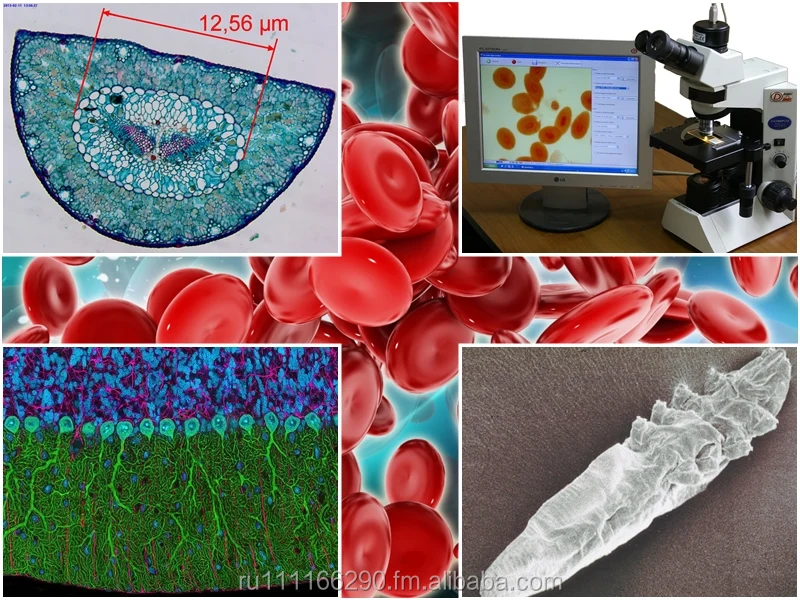

BIOSPECT 21 PRO

- Category:

- Supplier: Prointelgrup [Moldova]Prointelgrup [Moldova]Prointelgrup

RUB 444,557.82

In Stock